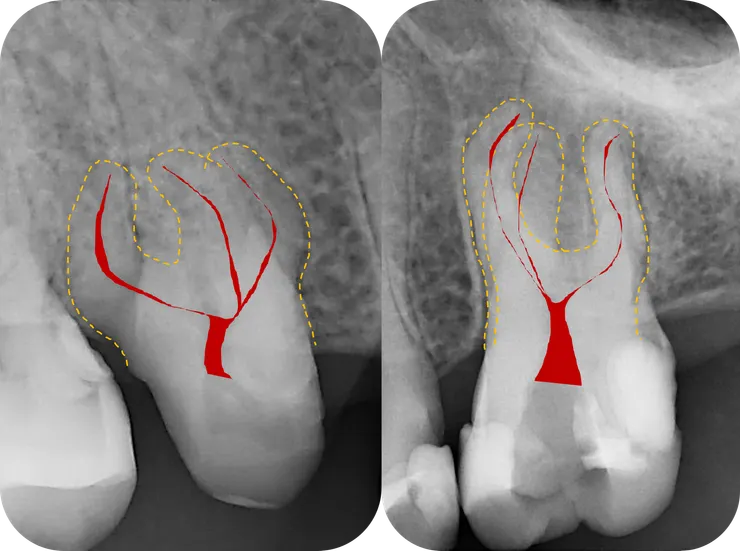

這篇的兩個主角分別是

左邊的 64 歲 16 (#20240611)

以及

右邊的 43 歲 26 (#20241224)

面對這種一看就知道絕非善類的 case, 最關鍵的步驟就是,在開始之前先仔細地把目標物清楚地描繪一番:

先如同橘色虛線般,將 root 的外型描繪出來 (相對單純的 palatal root 先忽略)。

然後再依據 root 的外型,將依稀可見的 canals 如同紅色線條般描繪出來。

腦中有了清晰的圖像後,才能以終為始的,一步步地完成後續的修形與封填。

(當然前提是必須有清晰的 initial PA, 而如果能藉由 CBCT 得到立體的架構那更好!)